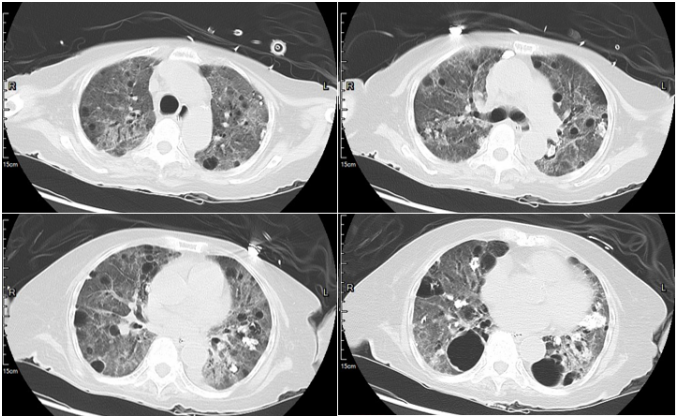

入院后完善CTPA检查:肺动脉稍增宽,所示肺动脉及主要分支未见确切充盈缺损;慢支-肺气肿改变,两肺多发肺大疱及炎症改变,两肺多发结节、斑结及钙化灶,多为陈旧性病变,双侧腋窝及纵隔多发淋巴结,两侧胸膜增厚,主动脉壁部分钙化,心影增大,心包少量积液(图3)

图片

图3  患者CTPA检查结果